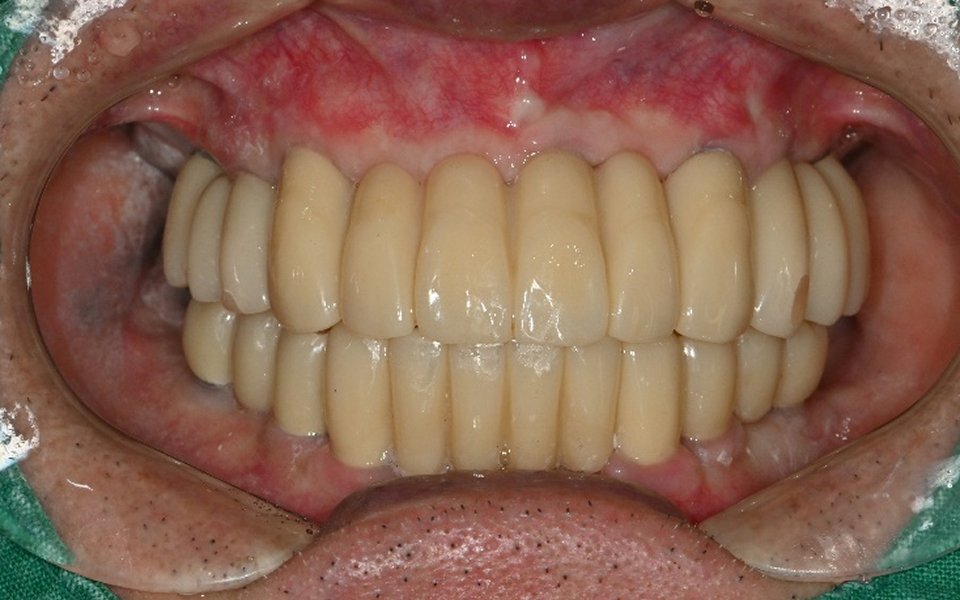

CASE 01 김** / 60대

전악임플란트

치료 시작 전 촬영 2024.01.24 | 치료 완료 후 촬영 2024.12.26

3 고정성 보철물로 수복 후 일상 회복

CASE 02 김** / 60대